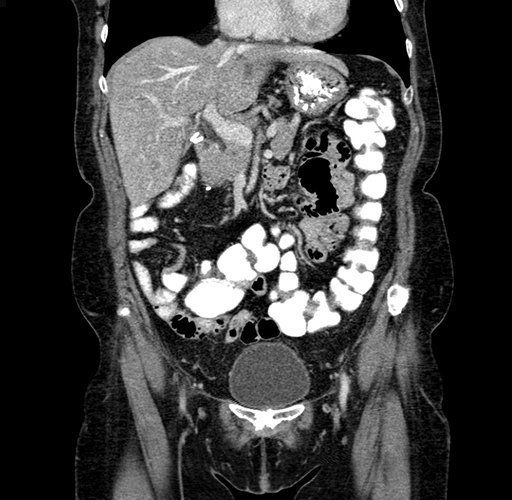

Pre-Chemo: Coronal Venous